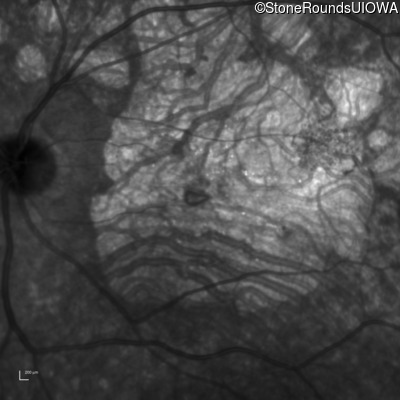

Age at visit: 30 years

This 30 year old man first noticed poor vision in dim light when he was five years old. His visual acuity began to fall in his early 20's.

Diagnosis & molecular findings

Macular Disease WDR19 His344Arg CAT>CGT Ser485Ile AGT>ATT AR